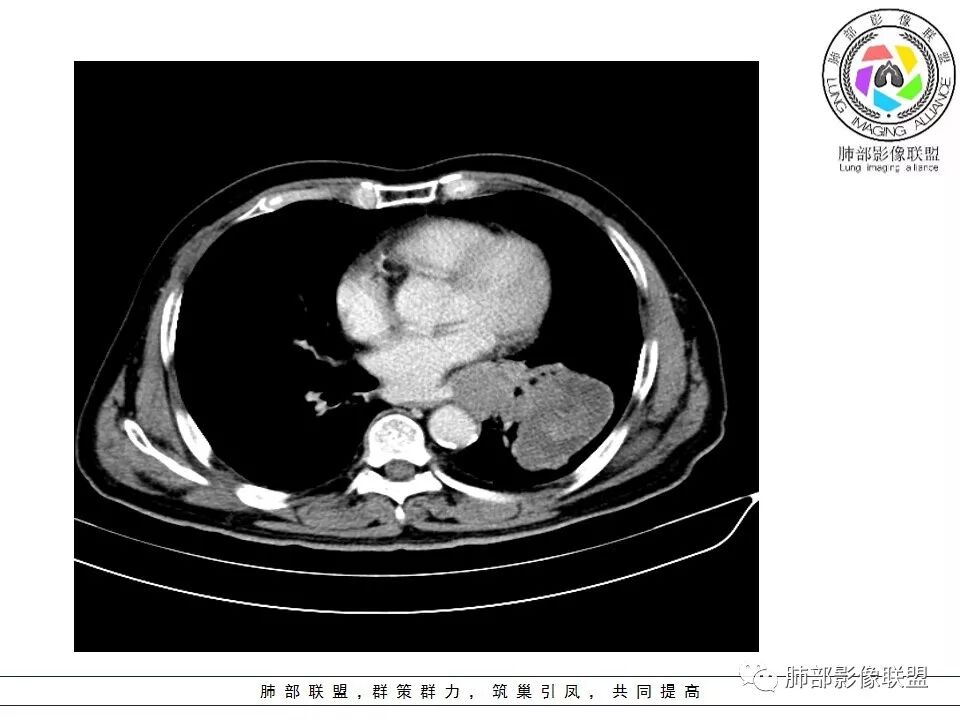

老年男性咳嗽,左下近肺门团块影,不规则强化伴坏死,左下肺静脉、支气管旁淋巴结转移受压、并侵犯左下支气管,考虑鳞癌,鉴别小细胞。

男,70岁,左下肺肿块影,分叶,增强有较大范围坏死,左肺门肿块影,跨叶,包绕支气管与肺门血管,致其狭窄考虑为淋巴结肿大,综合考虑为恶性肿块,鳞癌并左肺门淋巴结转移

肺门淋巴结有肿大,支气管内有肿物,这么大病灶没有坏死,我考虑神经内分泌癌或者小细胞肺癌。鳞癌不符合没看到明显阻塞

老年男性,咳嗽主诉,胸部ct左侧肺门新生物,支气管阻塞,不均匀强化,伴淋巴结肿大,考虑鳞癌,鉴别小细胞肺癌。

老年男性,左下占位,类圆丶浅分叶,无毛刺及胸膜凹陷征,各支气管狭窄,增强不均匀强化,左肺门淋巴结肿大考虑恶性,小>鳞

患者老年男性,以咳嗽就诊,胸CT:左肺下叶占位,病灶呈膨胀性生长,左肺下叶气管明显狭窄,病灶边缘光滑,并可见分叶,增强可见病灶内低密度区,病灶边缘强化。考虑恶性,鳞?肉瘤?

左下肺团块影,不规则强化伴坏死,左下肺静脉、支气管旁淋巴结转移,并侵犯左下支气管,考虑恶性病变,小细胞?

左肺主支气管下肿块,病变包绕并向腔内生长,无阻塞性肺炎,内部可见穿行血管,增强后可见实性明显强化,纵隔淋巴结肿大,老年男性,考虑:神经内分泌癌(类癌、小细胞癌),淋巴瘤,鳞癌

病史:男,70岁,咳嗽;影像:肺门淋巴结,淋巴结内血管毛糙不规则,静脉期,转移大,左心房左下静脉下支是否有累及。主体病灶,呈扇形,沼泽样,指状突起。肺气肿并不明显,左侧少许,左上叶支气管狭窄,肺窗点状凸起,纵膈窗并没有,考虑淋巴结压迫所致。老王曾经说过,小细胞来不及跑得快,胸膜目前没有积液是否是这个原因?诊断:恶性,小细胞肺癌;鉴别:鳞癌,不太像,其他神经类分泌恶性肿瘤;处置:经皮穿刺或EBUS。

左下肺占位性病变,伴肺门淋巴结肿大,强化示不均匀明显强化,可见边界不清坏死区,考虑恶性肿瘤!病灶缺乏分叶及毛刺,整体圆顿,病理倾向大细胞!

左下肺肿块,不均匀强化,其内可见坏死或粘液,更多考虑坏死,左下肺支气管堵塞,左肺门多发肿大淋巴结,左下肺癌,鳞癌可能性大鉴别于小细胞癌

病灶从外向里长,气管狭窄,血管受侵犯,肺门纵膈淋巴结肿大,考虑恶性,首先考虑小细胞癌

左下肺占位伴肺门淋巴结肿大,病灶呈膨胀性生长,左肺下叶气管明显狭窄推移,病灶边缘光滑,并可见分叶,增强可见坏死,病灶边缘强化,阻塞性肺炎不明显,恶性没问题,考虑低分化腺癌,鉴别神经内分泌肿瘤,无冰冻感觉,坏死明显,小细胞不支持,排除大细胞与类癌

老年男性,症状轻。左肺下叶类圆形肿块,边界清楚,分叶不明显,其内无空泡征,边缘无毛刺及胸膜牵拉,远端无阻塞性肺炎。左肺门影增大。增强扫描左肺下叶肿块可疑轻度强化(无平扫对比),局部见小尾巴征。左肺门区见不规则形团块,似多个结节融合,肺动脉受压穿行于病灶中,形成冰冻肺门感觉,局部层面似见肺门区团块与左肺下叶肿块相连。综合考虑小细胞肺癌(SCLC)。

左肺下叶肿块,边缘膨隆,分叶略浅,占位效应明显,远端没有明显花花草草,其内部不均匀强化,坏死边界不清,可见受累的强化血管穿行,是否有钙化?没有平扫,不清楚;同侧肺门淋巴结受累,包绕支气管生长,并突入下叶支气管,导致管腔闭塞及狭窄,考虑恶性没问题,肿瘤既有由外向内生长侵犯又有冰山征的感觉,小>类癌>低分化腺>鳞

病灶从外向内生长,气管狭窄,血管受侵犯,肺门纵膈淋巴结肿大,考虑恶性,腺癌。鉴别小细胞肺癌。

左下肺占位,边缘分叶彭隆,远端无明显阻塞性炎性,考虑外朝内生长为主,增强扫描边缘及病灶内均可见强化,血管破坏。考虑恶性,间叶组织来源,肉瘤?

段支气管管壁破坏比较明显了,小细胞可以破坏力这么强吗?

左肺下叶肿块,内部坏死明显,整体从外向内生长,下叶支气管及舌叶支气管被包绕生长,肺门区淋巴结肿大,坏死。远端无明显阻塞及不张,综合来看,恶性肯定,肺癌,整个病灶有分别有支持小细胞、鳞癌,腺癌及肉瘤样癌的地方,但又不典型,以低分化腺癌或肉瘤样癌或混合性癌(腺癌小细胞混合,低化分腺鳞癌混合),神经内分泌癌可能性大,单纯的鳞癌或小细胞癌有可能,但确实不典型了。至于间叶来源的恶性肿瘤,很少这样从向外内生甚至包绕支气管壁生长,再加上相对罕见,可能性小。

腔外浸润为主,腔内无明显堵塞,原发肿块推移支气管为主,边缘光滑,轻微分叶,肺门引流区淋巴结肿大,而纵隔淋巴结无明确受累,综合考虑,癌:低分化腺癌?大细胞癌?肉瘤样癌?间叶组织肿瘤:肺肉瘤,罕见

左肺门乱乱的,有血管受压表现,有支气管腔内占位表现,肺门淋巴结肿大肯定是有的;左肺下叶见一巨大包块,边缘光滑,内侧又一个切迹,考虑是病变受到了小叶间隔阻挡造成的其内部大部分不强化,但有局部一小片强化;壁不均匀环形强化,总体较薄;周围没有阻塞性肺炎,感染性病变应该是不考虑的,因为周围清楚,也没有感染的症状,还是考虑肿瘤性病变;关键是它边缘光滑,内部应该是坏死,但有强化提示坏死不彻底,这么大了,边缘恶性征象不明显,不符合腺癌,鳞癌呢也不太符合,阻塞性肺炎没有,坏死太明显了,这么大,边缘光滑,坏死明显,符合肉瘤和肉瘤样癌,不除外小细胞肺癌

南边:病灶分为两大块,外围囊实性大肿块,支气管关系不密切,内带多发淋巴结,侵犯支气管、肺血管,恶性没问题,按理间叶为主,或不典型的癌,这不是一个中央型的肺癌,是外朝内进展的,奇怪的是边界这么清楚光滑,一般癌肉瘤、肉瘤类多,其次才是癌,远端也没有阻塞,大方向是这样,恶性,间叶来源?或者混合,恶性程度较高,鉴别就是结核,因为结核是妖

1.左肺下叶近肺门区肿块,肿块外围大,内带小,提示外围向中央生长,符合周围型SCLC沿支气管方向生长。

2.病灶边缘光滑,未见明显分叶、毛刺,符合神经内分泌癌、癌肉瘤及间叶来源肿瘤。

3.病灶内密度偏低,穿行血管未见明显异常,轻度不均匀强化,为乏血供病灶。病灶内可疑坏死区,未见空洞;乏血供符合SCLC,但坏死区不符合。

4.病灶区支气管以受压推移为主,管腔不规则,腔内通而不畅,提示病灶粘膜下为主,符合SCLC迁徙蔓延或间叶来源肿瘤。

5.病灶内有血管走行,血管局部受压,但是强化考虑为乏血供,提示病灶内肺动脉并不是供血血管,只是病灶侵袭性强把血管包埋而已,为血管包埋征;血流面光滑,血管包埋符合SCLC。

6.左肺门淋巴结肿大,与病灶局部融合分界不清,呈冰冻肺门;而纵隔内未见肿大淋巴结,冰冻肺门符合SCLC,但是病灶主体那么大,纵隔内没有明显肿大淋巴结,不是很符合SCLC娘小崽大的特点。

7.未见明显阻塞性炎症及阻塞性肺不张,更加提示病灶从外围向中央侵犯,符合SCLC罕见阻塞性肺不张。